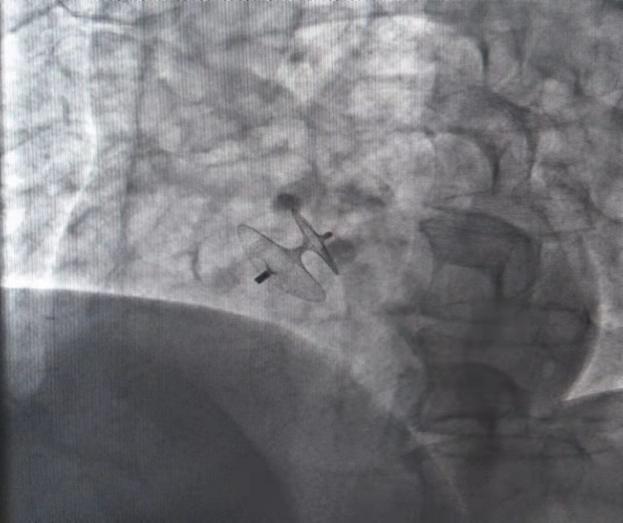

手术团队在刘先生局麻状态下,经股静脉穿刺,建立封堵器输送系统,心脏超声显示:封堵效果良好,无明显残余分流,牵拉实验证实封堵器位置稳定,成功将刘先生的威胁解除。术后转入心血管科CCU,采用中西医结合综合管理治疗措施,包括口服中药自制制剂、穴位贴敷、耳穴压豆等中医特色疗法,刘先生经过治疗后很快便康复出院了。在出院后电话随访时,了解到困扰刘先生多年的头晕头痛再未发作。

陈守宏主任医师、邵中兴副主任医师在手术过程中

封堵器及介入封堵示意图